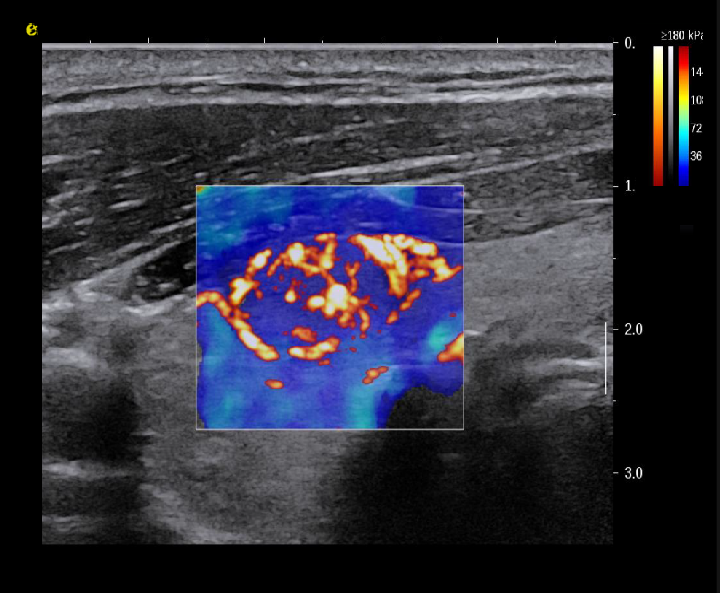

实时剪切波弹性成像

评估组织的软硬,并且提供定量数值,从而提示组织的良恶性。

image.png

鉴别诊断、精准分级、定量评价、穿刺引导、疗效评估、随访观察

恶性占位常常向周边组织进行侵润及扩散,二维很难观察到浸润部分的边界。使用实时剪切波成像能够对占位及周边组织进行硬度评估,通过颜色编码来区分不同组织的硬度信息,直观的观察占位组织的边界信息,更方便区分占位组织和正常组织的边界,准确评估消融范围。